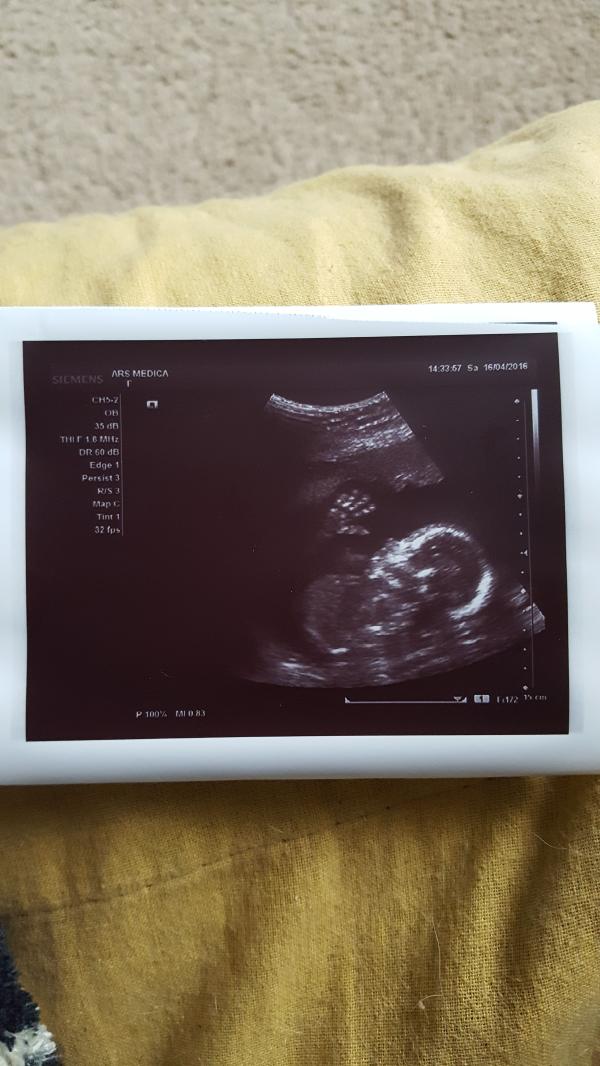

Родителям рассказали только в 3 месяца😶 И то не рассказали а показали. Придумали идею как будто родителям письмо пришло, а в письме первое узи😉 Мои родители не сообразили что за фотография в конверте, хотя может и я бы не сообразила увидев только маленького червяка на фото😏 Мама собиралась уже выкидывать конверт с фото, но я настойчиво говорю "уверена что хочешь выкинуть?".Он не понимала что я от нее хочу, долго всматривалась а когда поняла, в слезы🙂 Свекровь более догадливая, сразу все поняла ну и конечно же и тут без слез не обошлось😁 Но это настолько все мило было. Как вспомню, умиляюсь.

Кроха по узи была на 2 неделе больше срока. Все было хорошо, но в 31 неделю поставили "преждевременное созревание плаценты" 3 из 3. ПДР 15 сентября 2016.